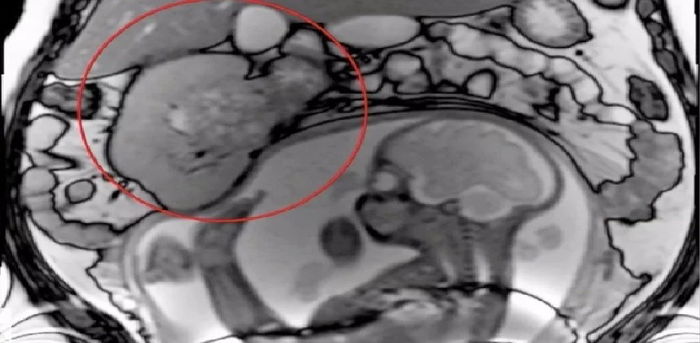

Imbasan MRI menunjukkan tumor tersebut betul-betul bersebelahan anaknya. | Kredit gambar: SWNS/screengrab

Tumor dalam kandungan Susan itu turut memeranjatkan pekerja di Guy’s and St Thomas’ Hospital. Semasa pemeriksaan, mereka mendapati yang mereka tidak boleh menggunakan imbasan CT ataupun biopsibuntuk mengesan punca tumor tersebut.

Susan menerangkan mengapa perkara itu terjadi. “Nasib baik imbasan MRI biasa menunjukkan tumor tersebut tidak membesar dan pasukan di Guy’s and St Thomas membuat keputusan yang saya tetap masih selamat untuk hamil sambil dipantau dengan teliti.